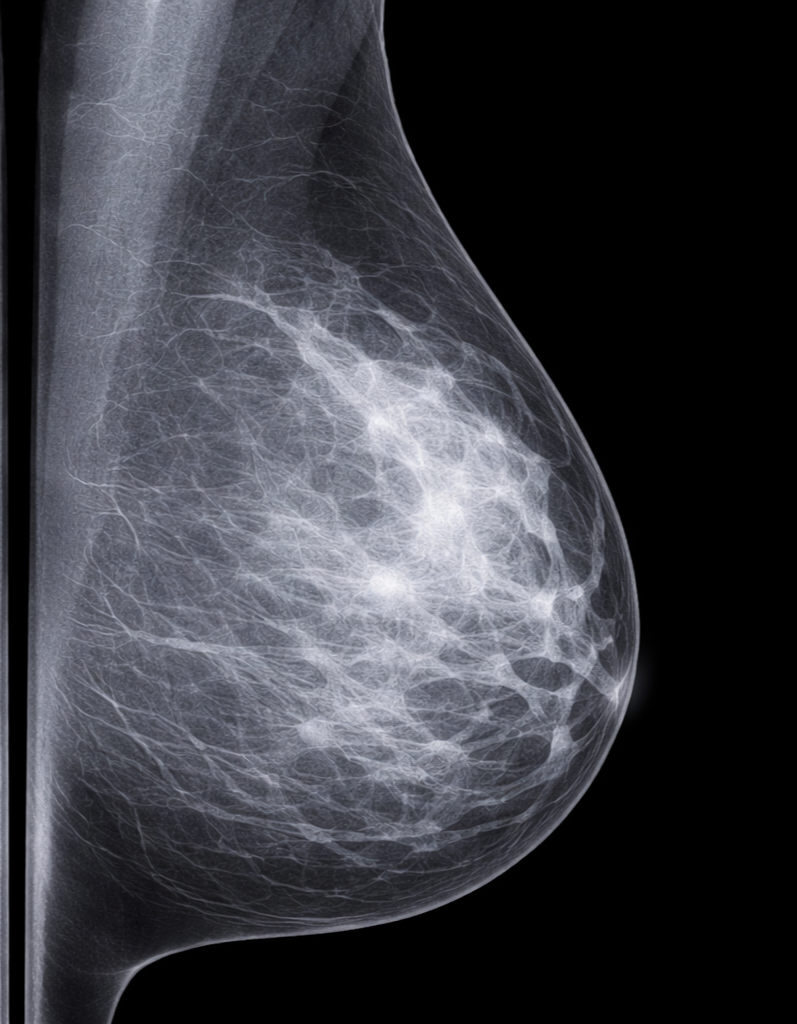

Diagnostic Imaging

To help you learn diagnostic imaging pearls for common primary care presentations